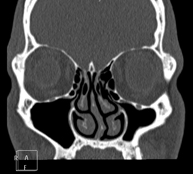

- Paranasal Sinuses CT

Radiological test that provides high definition anatomical images of the paranasal sinuses using CT (Computed Tomography) equipment. Indicated for: headache, mucus, facial infections.